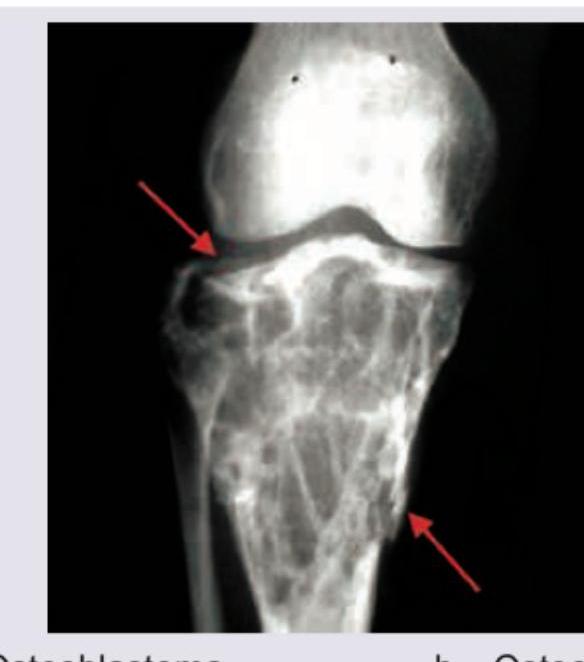

101. Identify the bone tumor:

Explanation: ***Aneurysmal bone cyst*** - The image shows an **expansile, lytic lesion** in the metaphysis of the tibia, with a **thin sclerotic rim** and **soap bubble appearance**, which is characteristic of an aneurysmal bone cyst. - The lesion extends close to the **epiphyseal plate** but generally respects it, and the presence of internal trabeculations often gives it a multiloculated appearance. *Osteoblastoma* - This lesion is typically a **well-circumscribed, lytic lesion** often associated with a **sclerotic rim**, but it usually presents as a nidus greater than 2 cm, frequently in the spine or long bones, and is less expansile than what is seen here. - While it can be destructive, the **multiloculated, expansile appearance** with distinct fluid levels (not directly visible on plain X-ray but implied by "soap bubble") is not typical for osteoblastoma. *Osteoclastoma* - Also known as **Giant Cell Tumor of Bone**, this tumor is typically an **epiphyseal lesion**, extending to the subarticular bone, often described as an **expansile osteolytic lesion** without a sclerotic rim. - The lesion in the image is more metaphyseal and shows a well-defined sclerotic border with internal septations, not the typical "soap bubble" appearance of ABC or the purely lytic destructive nature of an osteoclastoma. *Chondrosarcoma* - Chondrosarcomas are malignant tumors characterized by the formation of cartilage, often presenting as **lytic lesions with calcifications** (popcorn or ring-and-arc patterns) and cortical destruction, but typically lack the multiloculated, expansile, "soap bubble" appearance of an aneurysmal bone cyst. - While they can be expansile, the **radiographic features** in the image, particularly the internal architecture and clear margination, are not typical for chondrosarcoma.